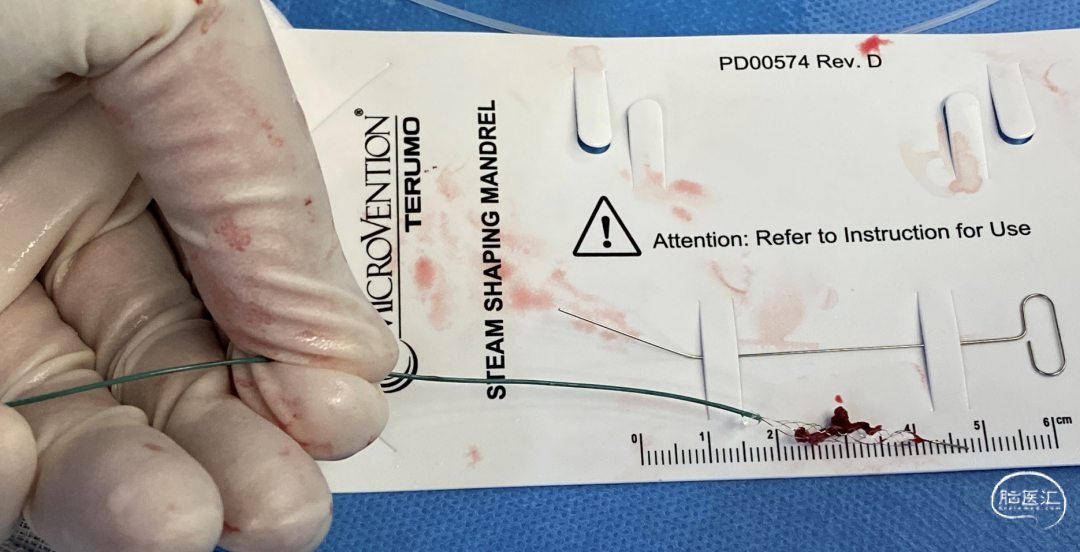

微导管:headway 17

headway 17微导管到位

JRecanTM 2.5mm*15mm进入血管远端,小尺寸支架对远端血管损伤小。释放于闭塞段,大网眼设计,充分嵌入血栓